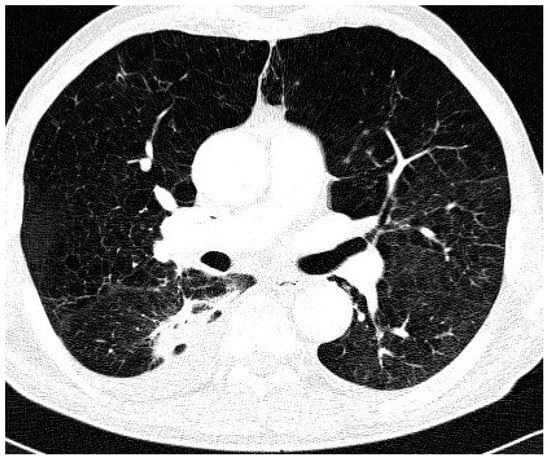

| Type of Chest CT Changes | Total Population No. 36 | NTM-LD No. 17 | Colonization No. 19 | p |

| Nodular/bronchiectasis No. (%) | 17 (47) | 8 (47) | 9 (47) | 0.03 |

| Infiltrations/cavities No. (%) | 6 (17) | 6 (35) | 0 (0) | |

| Non-specific No. (%) | 13 (36) | 3 (18) | 10 (57) | |